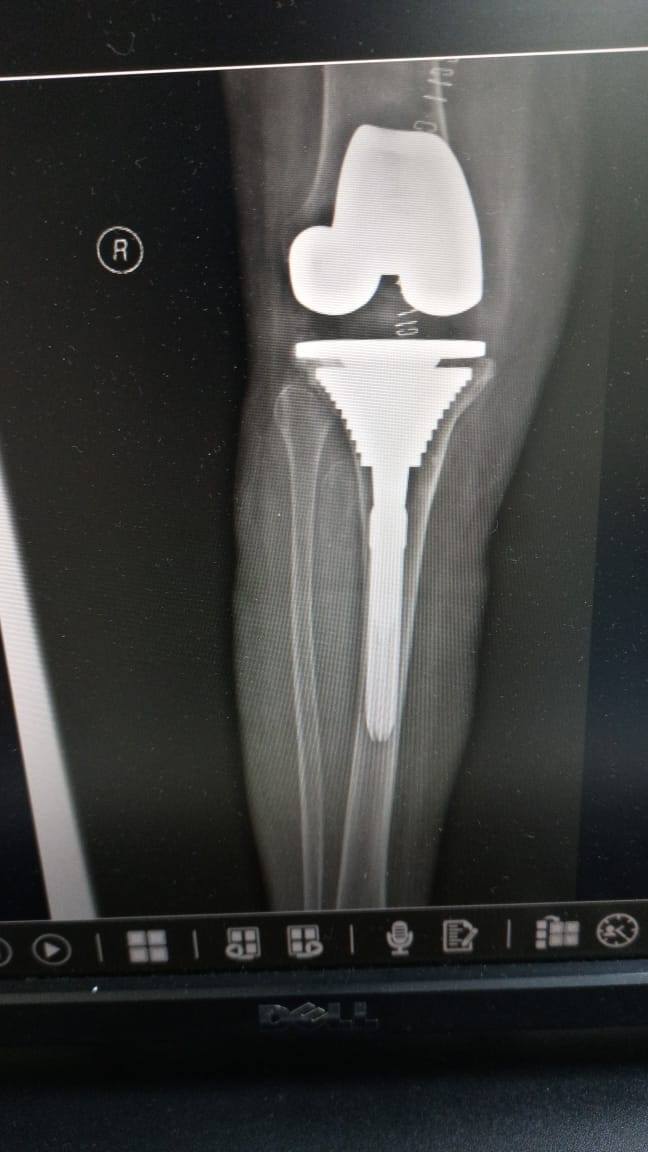

زراعة المفاصل الصناعية ورك و